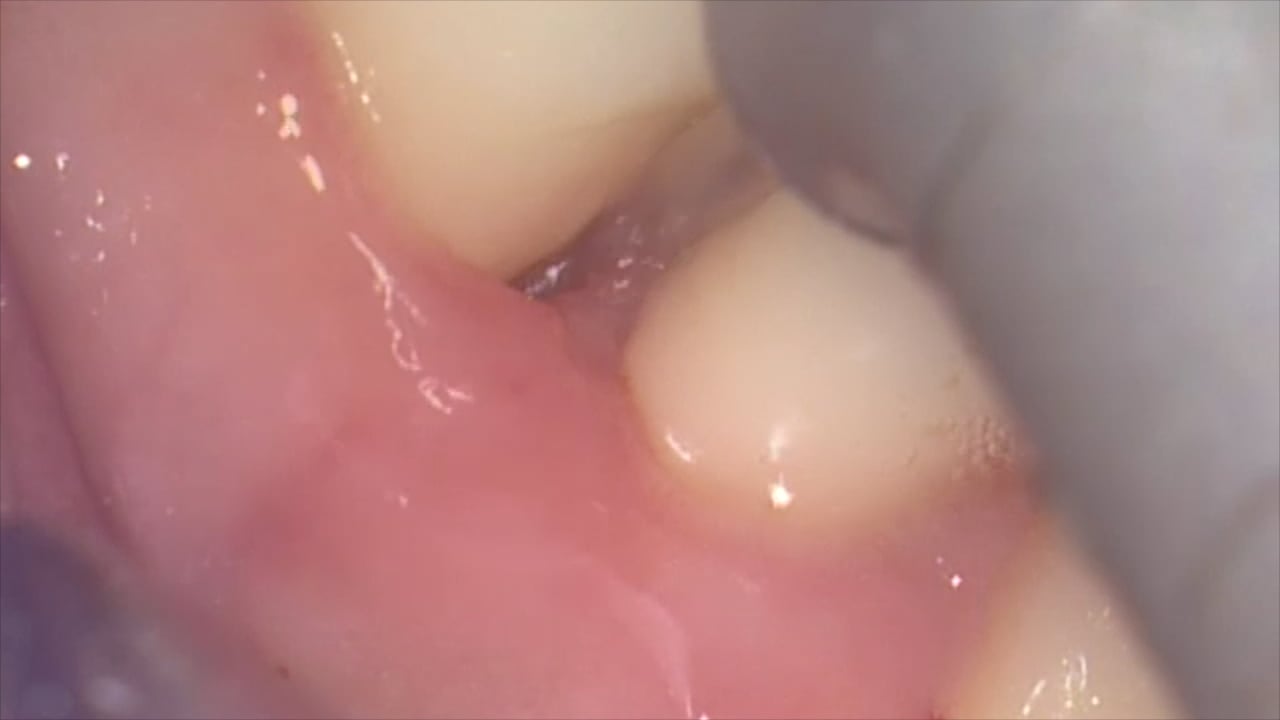

Technique d’assainissement parodontal microchirurgical assisté au LASER Er-Yag par le Dr. Fabrice Baudot (Montpellier) [av_video src=’https://vimeo.com/168053991′ format=’16-9′ width=’16’ height=’9′ av_uid=’av-yyue’]